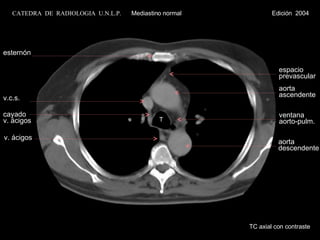

T esternón v.c.s.cayado v. ácigos v. ácigos espacio prevascular aorta ascendente ventana aorto-pulm. aorta descendente TC axial con contraste CATEDRA DE RADIOLOGIA U.N.L.P. Mediastino normal Edición 2004

T esternón v.c.s. cayado v. ácigos v. ácigos espacio prevascular aorta  ascendente ventana aorto-pulm. aorta descendente TC axial con contraste CATEDRA  DE  RADIOLOGIA  U.N.L.P.   Mediastino normal  Edición  2004